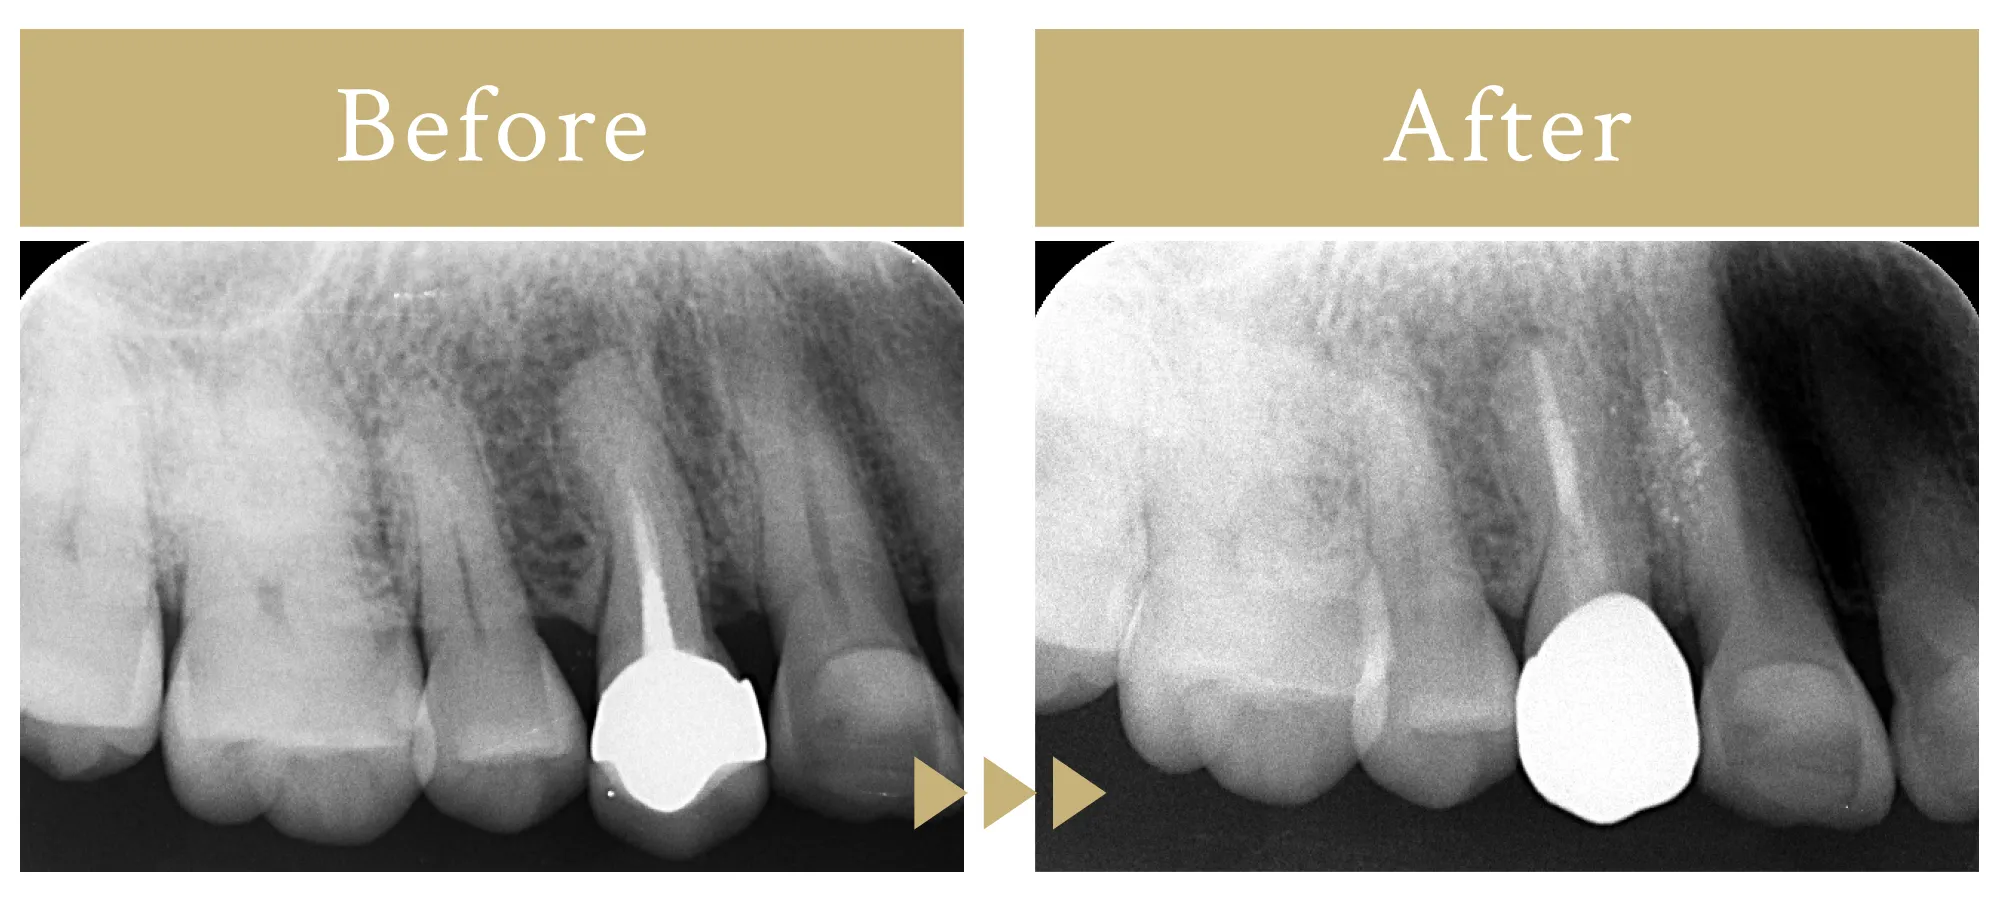

根尖性歯周炎に対しての感染根管再治療

70代女性

一度根管治療を行った歯の症状の再発、再感染に対して精密根管治療を行いました。

(根管治療終了後に補綴治療を行っています。)

10万円/約20日間

疼痛、腫脹、歯根破折、咬合時の違和感